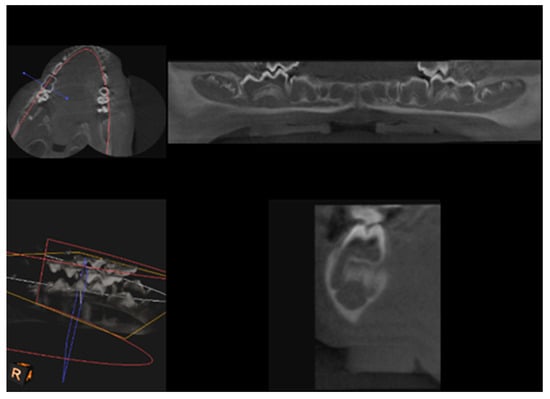

CBCT examination, with a Kodak 3000C 3D system (Kodak Dental Systems, Atlanta, GA, USA), together with Dental Imaging Software ver. 6.12.32 (Kodak Dental Systems, Atlanta, GA, USA), was performed before and immediately after germectomy and then again on the extracted jaws of the piglets after euthanasia with a voxel size of 160 μm, a 0.16 mm space between slices and a field of view of 13 × 10 cm, 90 kV and 4 mA. CT sections were used to assess the width and height of the bone, the thickness of the base plate, the tongue and vestibular side, the dimensions of the marrow cavities, and the height of the mandibular alveolar part. Four measurement planes were determined in the area from the first to the third milky premolars on the dentition side, and then, similarly to the manual measurements, measurement planes were determined for the operated side at the same distance from the line connecting the most distal points of the condylar process and the mandibular angle, in a line parallel to the lower edge of the mandibular shaft. Figure 3 and Figure 4 show an example of a CT scan image of a piglet’s mandible before (Figure 3) and after surgery (Figure 4) and Figure 5 and Figure 6 are diagrams of the external (Figure 5) and internal measurements (Figure 6) of the mandible of the piglets.

Figure 3.

An example of a CT scan image of a piglet’s mandible before surgery to remove the dental setae.